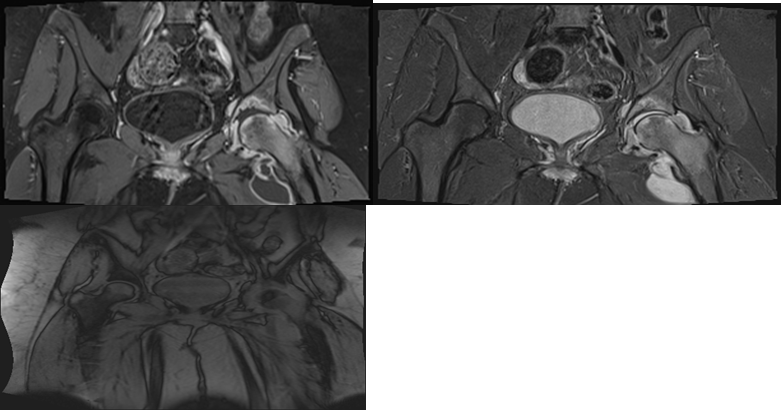

The MRI test revealed diffuse heterogeneous high-T2/low-T1 signal intensity involving the head and neck of the left femur and left acetabulum, with a surrounding thick synovium and enhancement postcontrast with joint effusion. Multiloculated high-T2-signal-intensity lesions were also observed medial and inferior to the left femur’s neck with ring enhancement, along with multiple reactive femoral lymph nodes. These findings are in line with septic arthritis of the left-hip joint (Figure 3).

Figure 3 MRI of the pelvic and proximal femurs show diffuse heterogeneous high T2 low T1 signal intensity involving the head and neck of the left femur as well as the left acetabulum with surrounding thick synovium with joint effusion. There are also multiloculated high T2 signal intensity lesions noted medial and inferior to the neck of the left femur with ring enhancement.